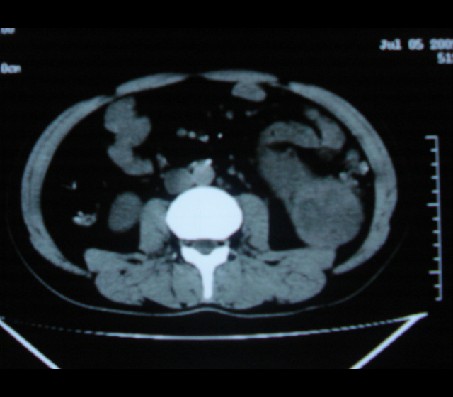

标题: CT20935:左肾占位,请会诊!

男性,35岁,ct号26189,左侧腰痛并血尿一天入院。